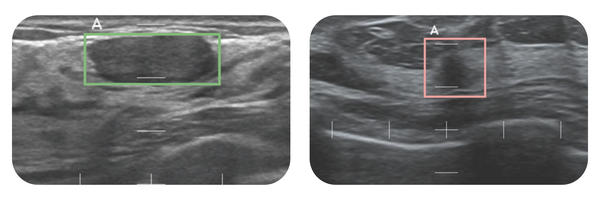

「スマートオピニオン METIS Eye」の検出結果イメージ

精密検査の必要性が疑われる場合は赤枠・疑われない場合は緑枠で表示